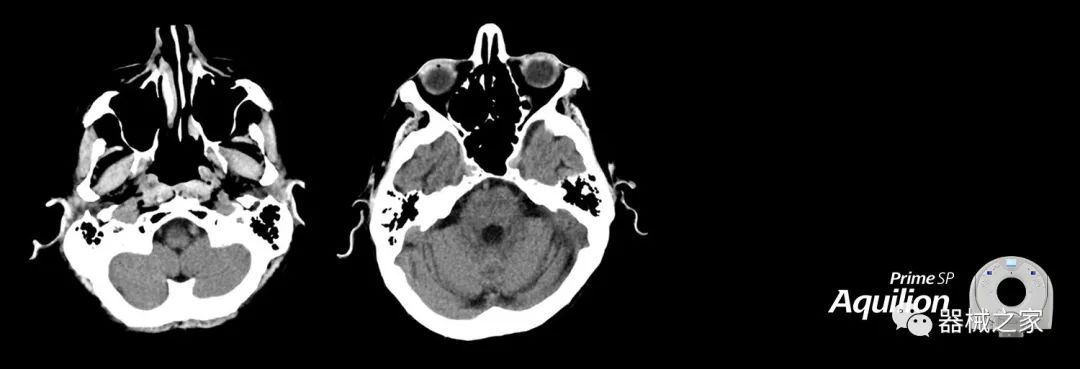

在以患者為中心的放射腫瘤學(xué)領(lǐng)域,計算機(jī)斷層掃描(CT)的可訪問性,可重復(fù)性和靈活性至關(guān)重要。為了建立這些價值,佳能醫(yī)療系統(tǒng)美國公司現(xiàn)在正在擴(kuò)大其放射腫瘤學(xué)CT模擬產(chǎn)品,包括Aquilion Prime SP和Aquilion Lightning 80高級CT系統(tǒng)。除了Aquilion LB之外,Aquilion Prime SP和Aquilion Lightning 80現(xiàn)在還包括放射治療(RT)選項,可為腫瘤學(xué)規(guī)劃提供高質(zhì)量的CT成像和精密工具。

Aquilion Prime SP使設(shè)施能夠處理具有挑戰(zhàn)性的案例,同時為員工提供快速,靈活和高效的解決方案。

佳能醫(yī)療的Aquilion Lightning 80掃描儀還以緊湊,經(jīng)濟(jì)的包裝提供高質(zhì)量的成像。Aquilion Lightning 80旨在可靠,高效地運(yùn)行,在繁忙的環(huán)境中生成高質(zhì)量的圖像。

兩個CT系統(tǒng)均采用0.5 mm x 80排PUREViSION探測器技術(shù)(可配置并從80-160現(xiàn)場升級),78 cm孔徑,50 cm視野,AIDR(自適應(yīng)迭代劑量減少)3-D和SEMAR(單個)能量金屬神器減少)技術(shù)。